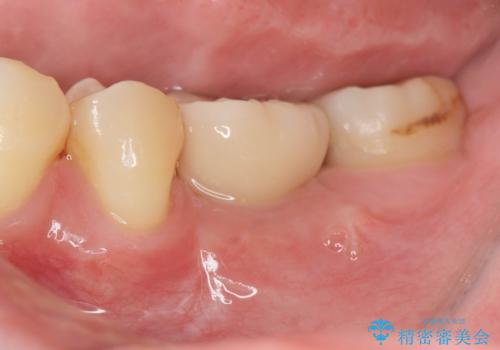

歯槽堤保存を併用し清掃性を高めたブリッジ治療

担当医 大元洋佑